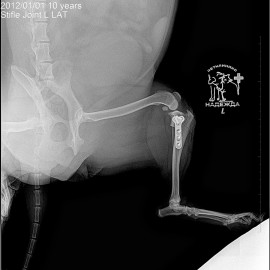

Наш пациент собака по кличке Буся.

Обратились с жалобами на хромоту на левую заднюю лапу.

Были проведены исследования, после которых был поставлен диагноз: разрыв передней крестообразной связки левого коленного сустава. Была проведена операция: TPLO.

Снимки 3-4 после операции.